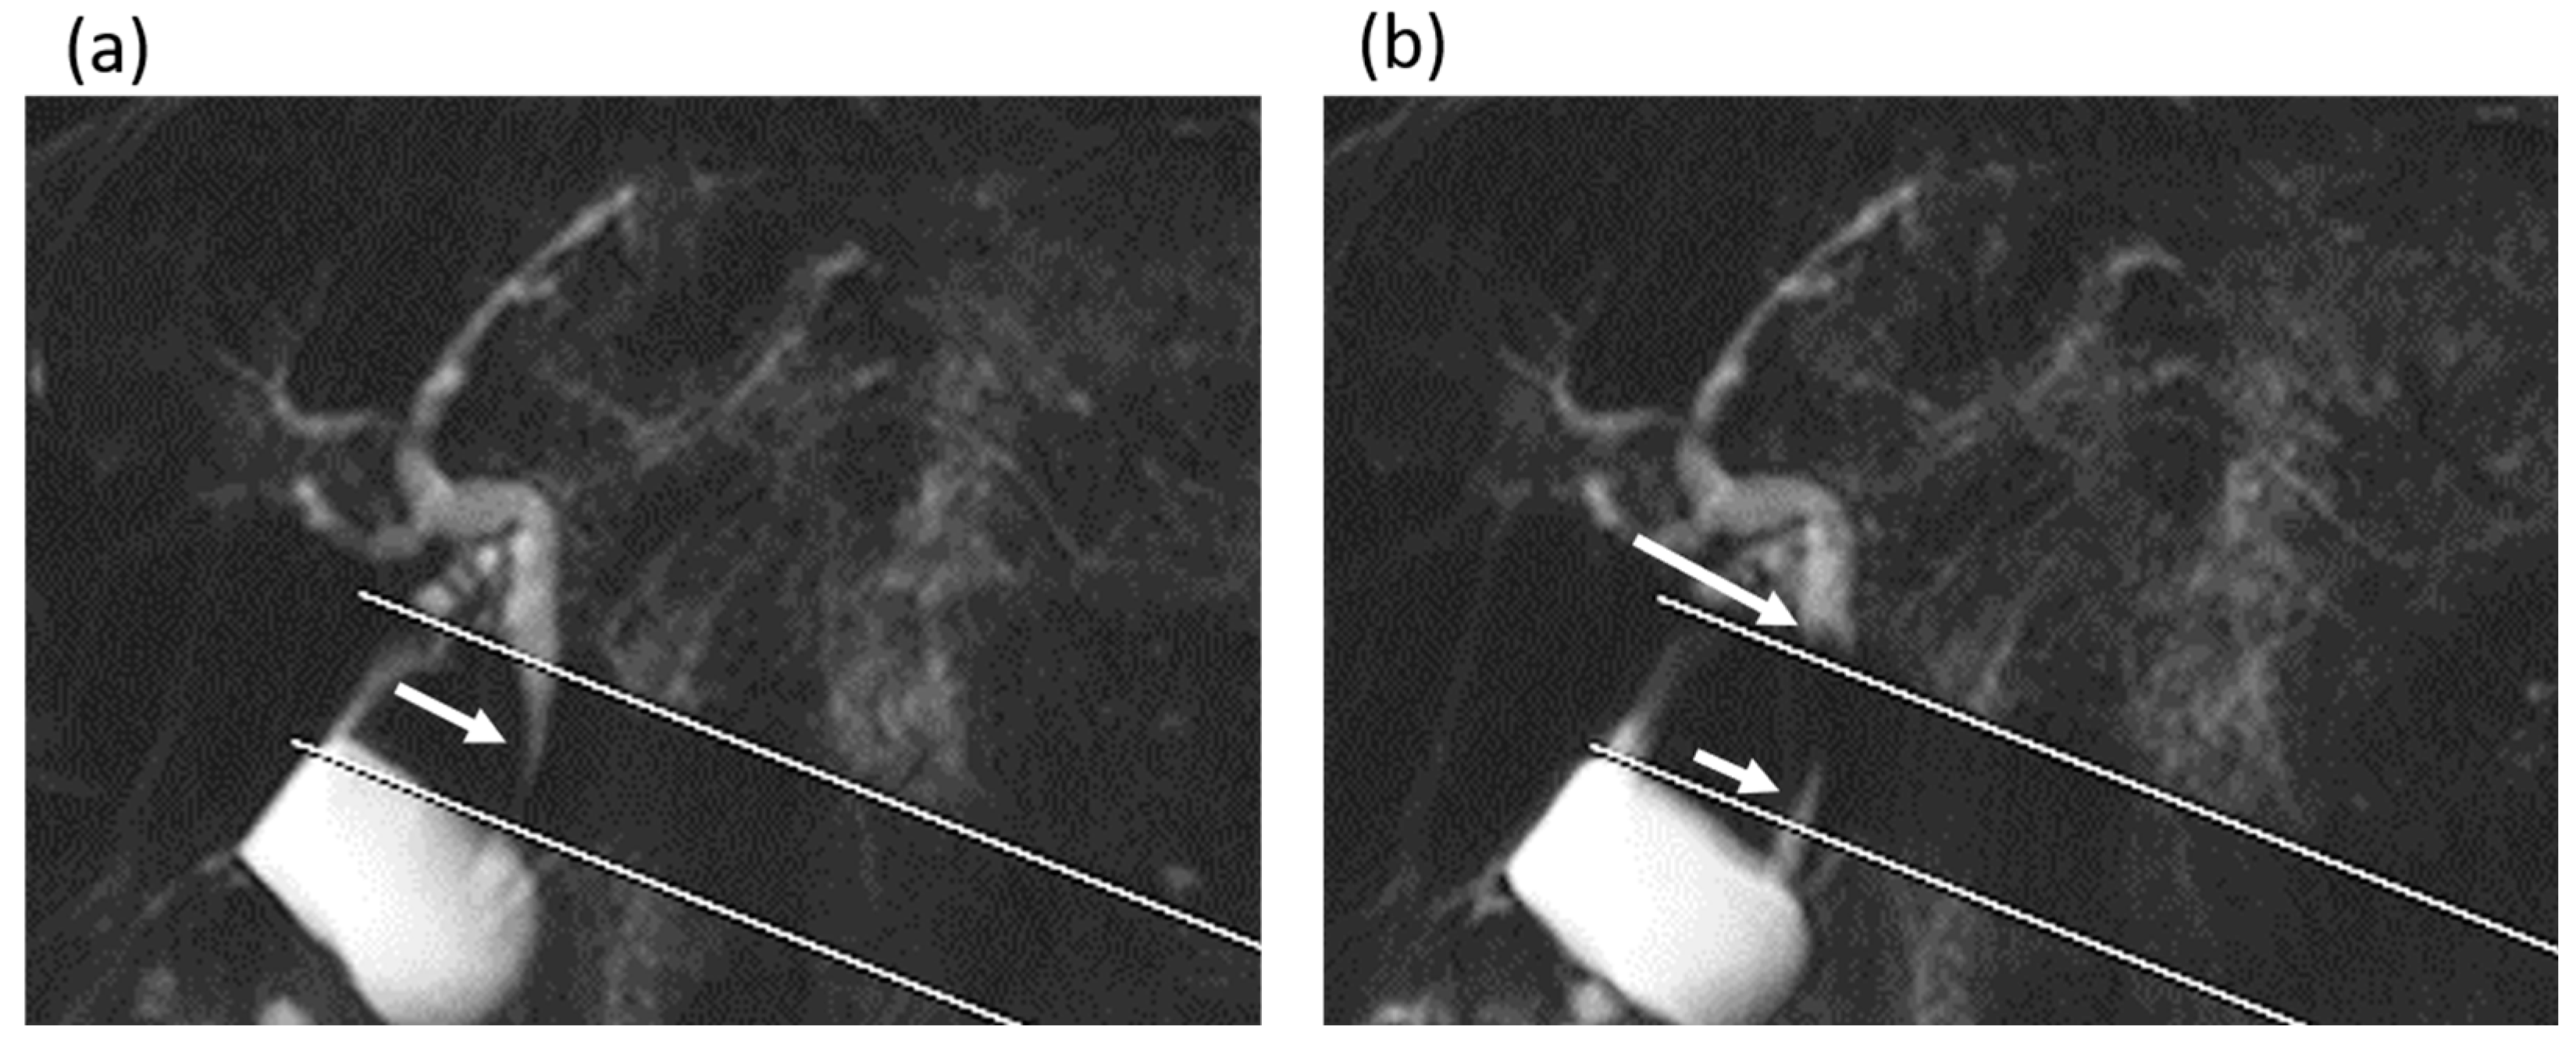

Figure 4.

A 75-year-old man in the gallstone group. (a,b) Cine-dynamic MRCP images with a spatially selective IR pulse. (a) The antegrade bile flow was shown as high signal intensity (arrow) within the area of the IR pulse, showing a grading score of 4. (b) The reverse bile flow was seen as low signal intensity outside the area of the IR pulse (long arrow) and was also observed as high signal intensity coming from duodenal papilla side into the area of the IR pulse (short arrow). The grading score of reverse bile flow was categorized as 2.